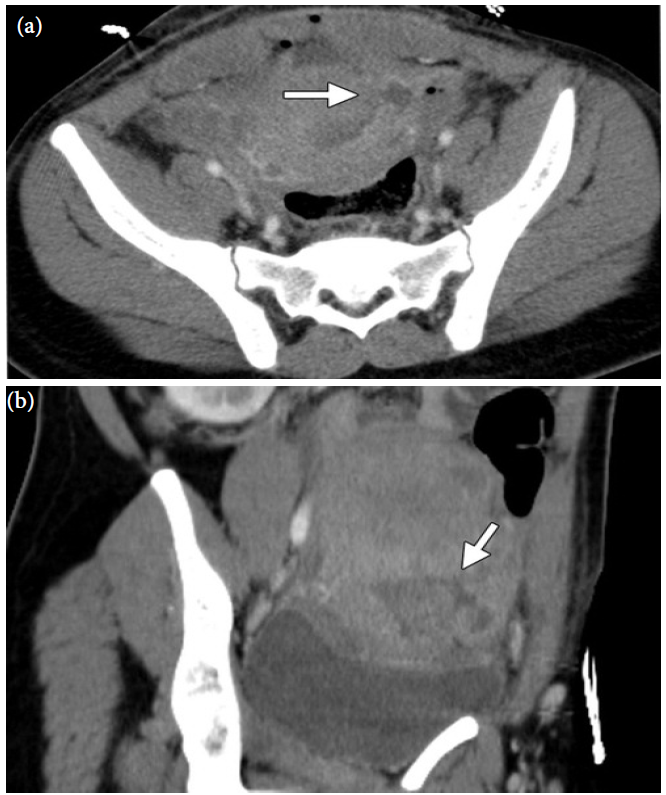

Figure 15: Contrast-enhance CT images taken in the axial (a) and coronal oblique (b) planes, 4 days post caesarean delivery. Disruption of the myometrium (arrow) in the left aspect of the lower uterine segment can be seen as a hypoattenuating band in the myometrium, with subsequent communication of the uterine cavity with a fluid collection in the left broad ligament and pelvis (Reprinted with permission) [5].